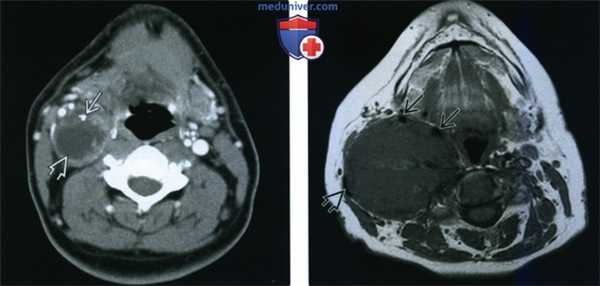

(Слева) КТ с КУ, аксиальная проекция. В сонном пространстве, сразу над подъязычной костью, определяется шваннома, преимущественно кистозного строения. Для крупных опухолей весьма типично наличие кист. Обратите внимание на редкие кальцификаты в передней стенке опухоли.

(Справа) МРТ Т1ВИ, аксиальная проекция. Крупная опухоль сонного пространства, которая смещает сонные артерии вперед и в медиальную сторону, а внутреннюю яремную вену - назад и в латеральную сторону. Интраоперационно было установлено, что опухоль происходит из периферического нерва и является злокачественной.